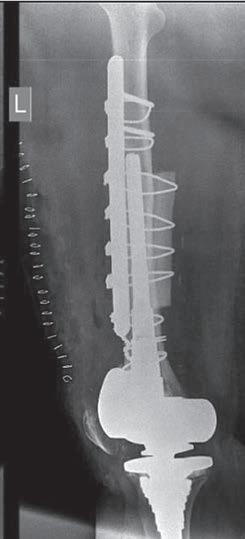

b

Rycina 14.2. Osteokondukcyjne pobudzenie zrostu kostnego belką i przeszczepami kości allogenicznej złamania okołoprotezowego kości udowej lewej po realoplastyce rewizyjnej stawu kolanowego; a) rentgenogram w projekcji przednio-tylnej (a-p), b) rentgenogram w projekcji bocznej (l).